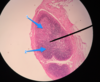

ID Tissue and Structures noted

Tonsil

- Germinal Center

- Nodule

- Epithelium

*Crypt not shown, but know it (refer to other tonsil slide)